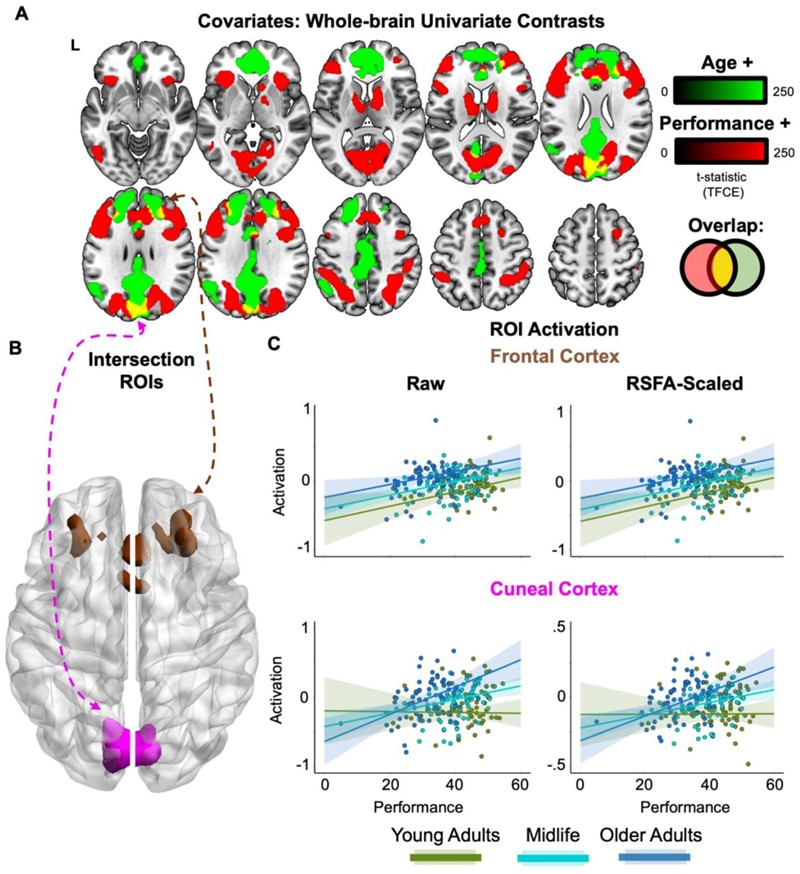

Dodatnom analizom uz pomoć strojnog učenja otkrivena su dva područja mozga koja kod starijih ljudi pokazuju veću aktivnost i povezana su s boljim učinkom prilikom rješavanja zadataka. Riječ je o cuneusu u stražnjem dijelu mozga i regiji u frontalnom korteksu. Ali od njih dvoje, samo je aktivnost u regiji cuneusa bila jače povezana s izvođenjem zadatka kod starijih i sadržavala je dodatne informacije o zadatku izvan MDN-a.

Iako nije jasno zašto bi se točno baš ovaj dio mozga trebao angažirati za ovaj zadatak, istraživači ističu da nam ova regija mozga obično pomaže da ostanemo usredotočeni na ono što vidimo. Starijim odraslim osobama često je teže nakratko se prisjetiti informacija koje su upravo vidjeli. Povećana aktivnost u cuneusu mogla bi značiti strategiju kojom starije osobe nadoknađuju slabije vizualno pamćenje.